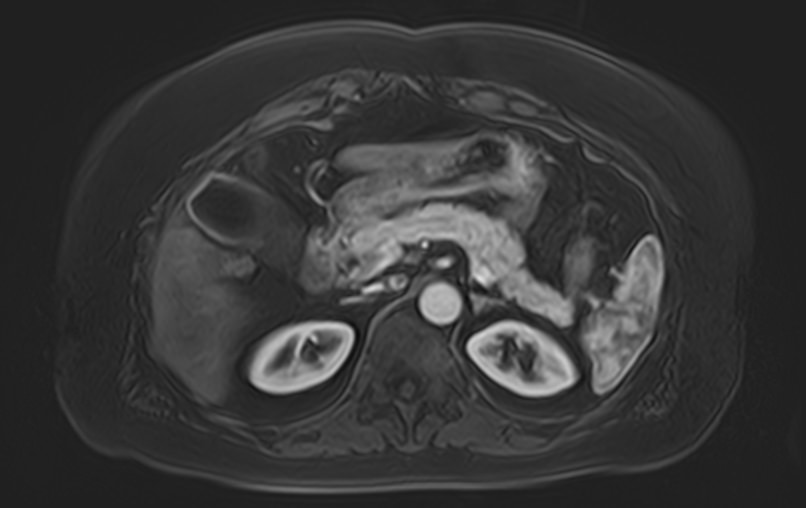

Для расширения возможностей диагностики, при необходимости уточнения характера патологических изменений, в случае подозрения на опухолевый процесс, дополнительно применяется внутривенное контрастное усиление.

Для этого в вену вводится контрастный препарат, содержащий соединения металла гадолиния (Магневист, Гадовист, Омнискан и др). Степень и характер накопления контрастного препарата в органах и тканях позволяет различать патологические процессы и дает возможность, в частности, диагностировать патологические очаги минимальных размеров, что бывает особенно важно в ранней диагностике опухолей.